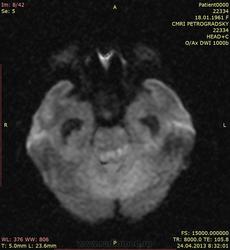

Лептоменигиальные метастазы

Пациентка 53 лет. Постепенно развилось нарушение сознания, на момент обследования в сопоре. В анамнезе - комбинированное лечение рака молочной железы.

Отдельный интерес представляет то, что происходит в мозжечке и левой теменной доле - чем именно представлены зоны изменения сигнала в ткани мозга? Термин "отек" все же несколько неконкретен. Тем более, что он осложнился в нашем случае окклюзией и вклинением.

Является ли этот отек венозным инфарктом, возникшим в результате поражения путей венозного оттока опухолевой тканью? Интересно мнение коллег.

Почему, это отек и есть. Но отек же разный бывает - вазогенный, цитотоксический, интерстициальный. В данном случае меня интересует как раз его происхождение.

Цитотоксический дал бы очень яркую диффузию, как при инфаркте.